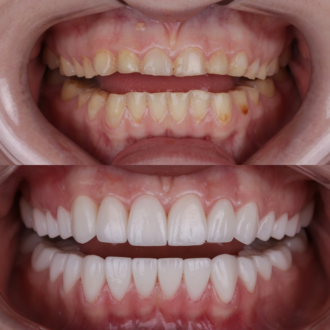

Произведена комплексная эстетическая реабилитация улыбки. Восстановлены правильные пропорции зубов, улучшено цвет и форму, гармонизирована улыбка с чертами лица. Сохранен максимальный объем собственных тканей — достигнут естественный и гармоничный результат.

Произведено: диагностику, цифровую планировку улыбки, моделирование формы зубов, минимально инвазивную подготовку, установку керамических реставраций E-max. Результат: гармоничная форма зубов, естественный цвет и прозрачность, правильная длина резцов, более открытая и выразительная улыбка с сохранением собственных тканей зуба.